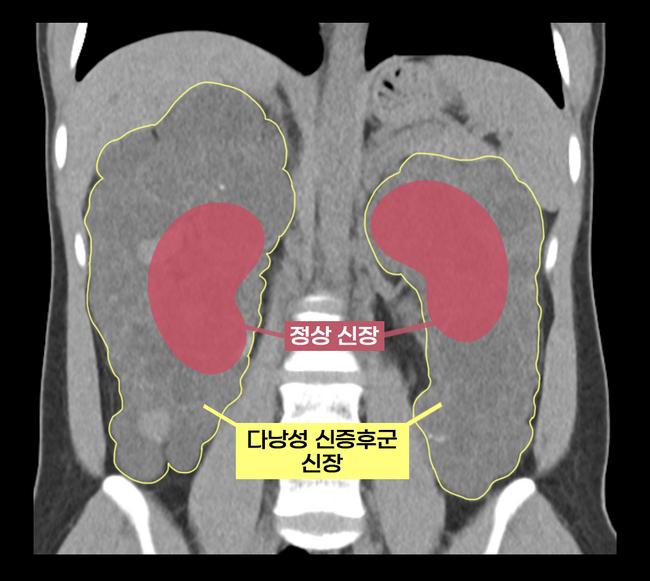

실제 다낭성 신증후군 환자의 신장과 정상 신장 비교 사진

다낭성 신증후군은 유전성 질환으로 양쪽 신장에 다수의 낭종이 발생해 신장이 커지고 만성 신부전으로 이어지는 병이다. 일반적인 만성 신부전 환자는 기존 신장을 남겨둔 채 이식을 진행하지만, 이 질환은 신장이 너무 커져 새로운 신장이 들어갈 공간이 부족하고, 낭종 감염 및 암 발생 등의 위험 때문에 양쪽 신장을 제거한 뒤 이식을 해야 한다. 그만큼 수술 난도가 높아, 지금까지는 대부분 개복 수술이 시행돼왔다.